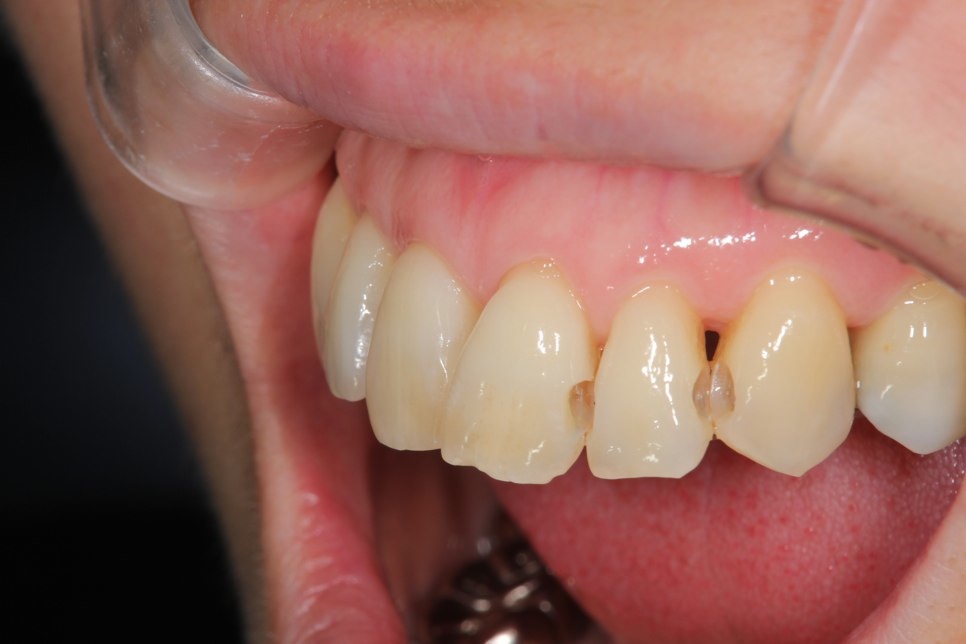

左右のダイレクトボンディング

費用5万円×4本

リスクとして欠ける可能性がある(修復可能)。